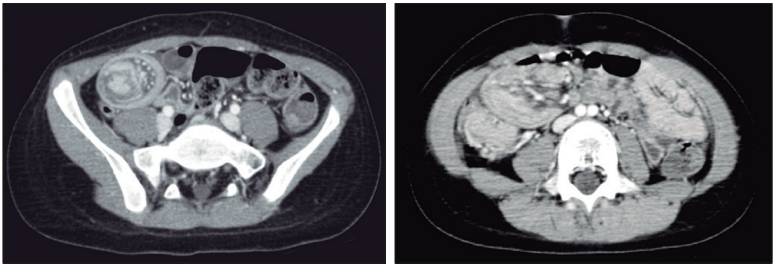

Posteriormente, se le indicó una tomografía computada multidetector abdominal sin contraste, que evidenció, a nivel del hemiabdomen derecho, una masa con densidad de partes blandas de aspecto de diana, asociada a escasa cantidad de líquido adyacente e ingurgitación de vasos mesentéricos (Figuras 3 y 4).

Figuras 3 y 4. Tomografía computada con contraste endovenoso en cortes axiales.